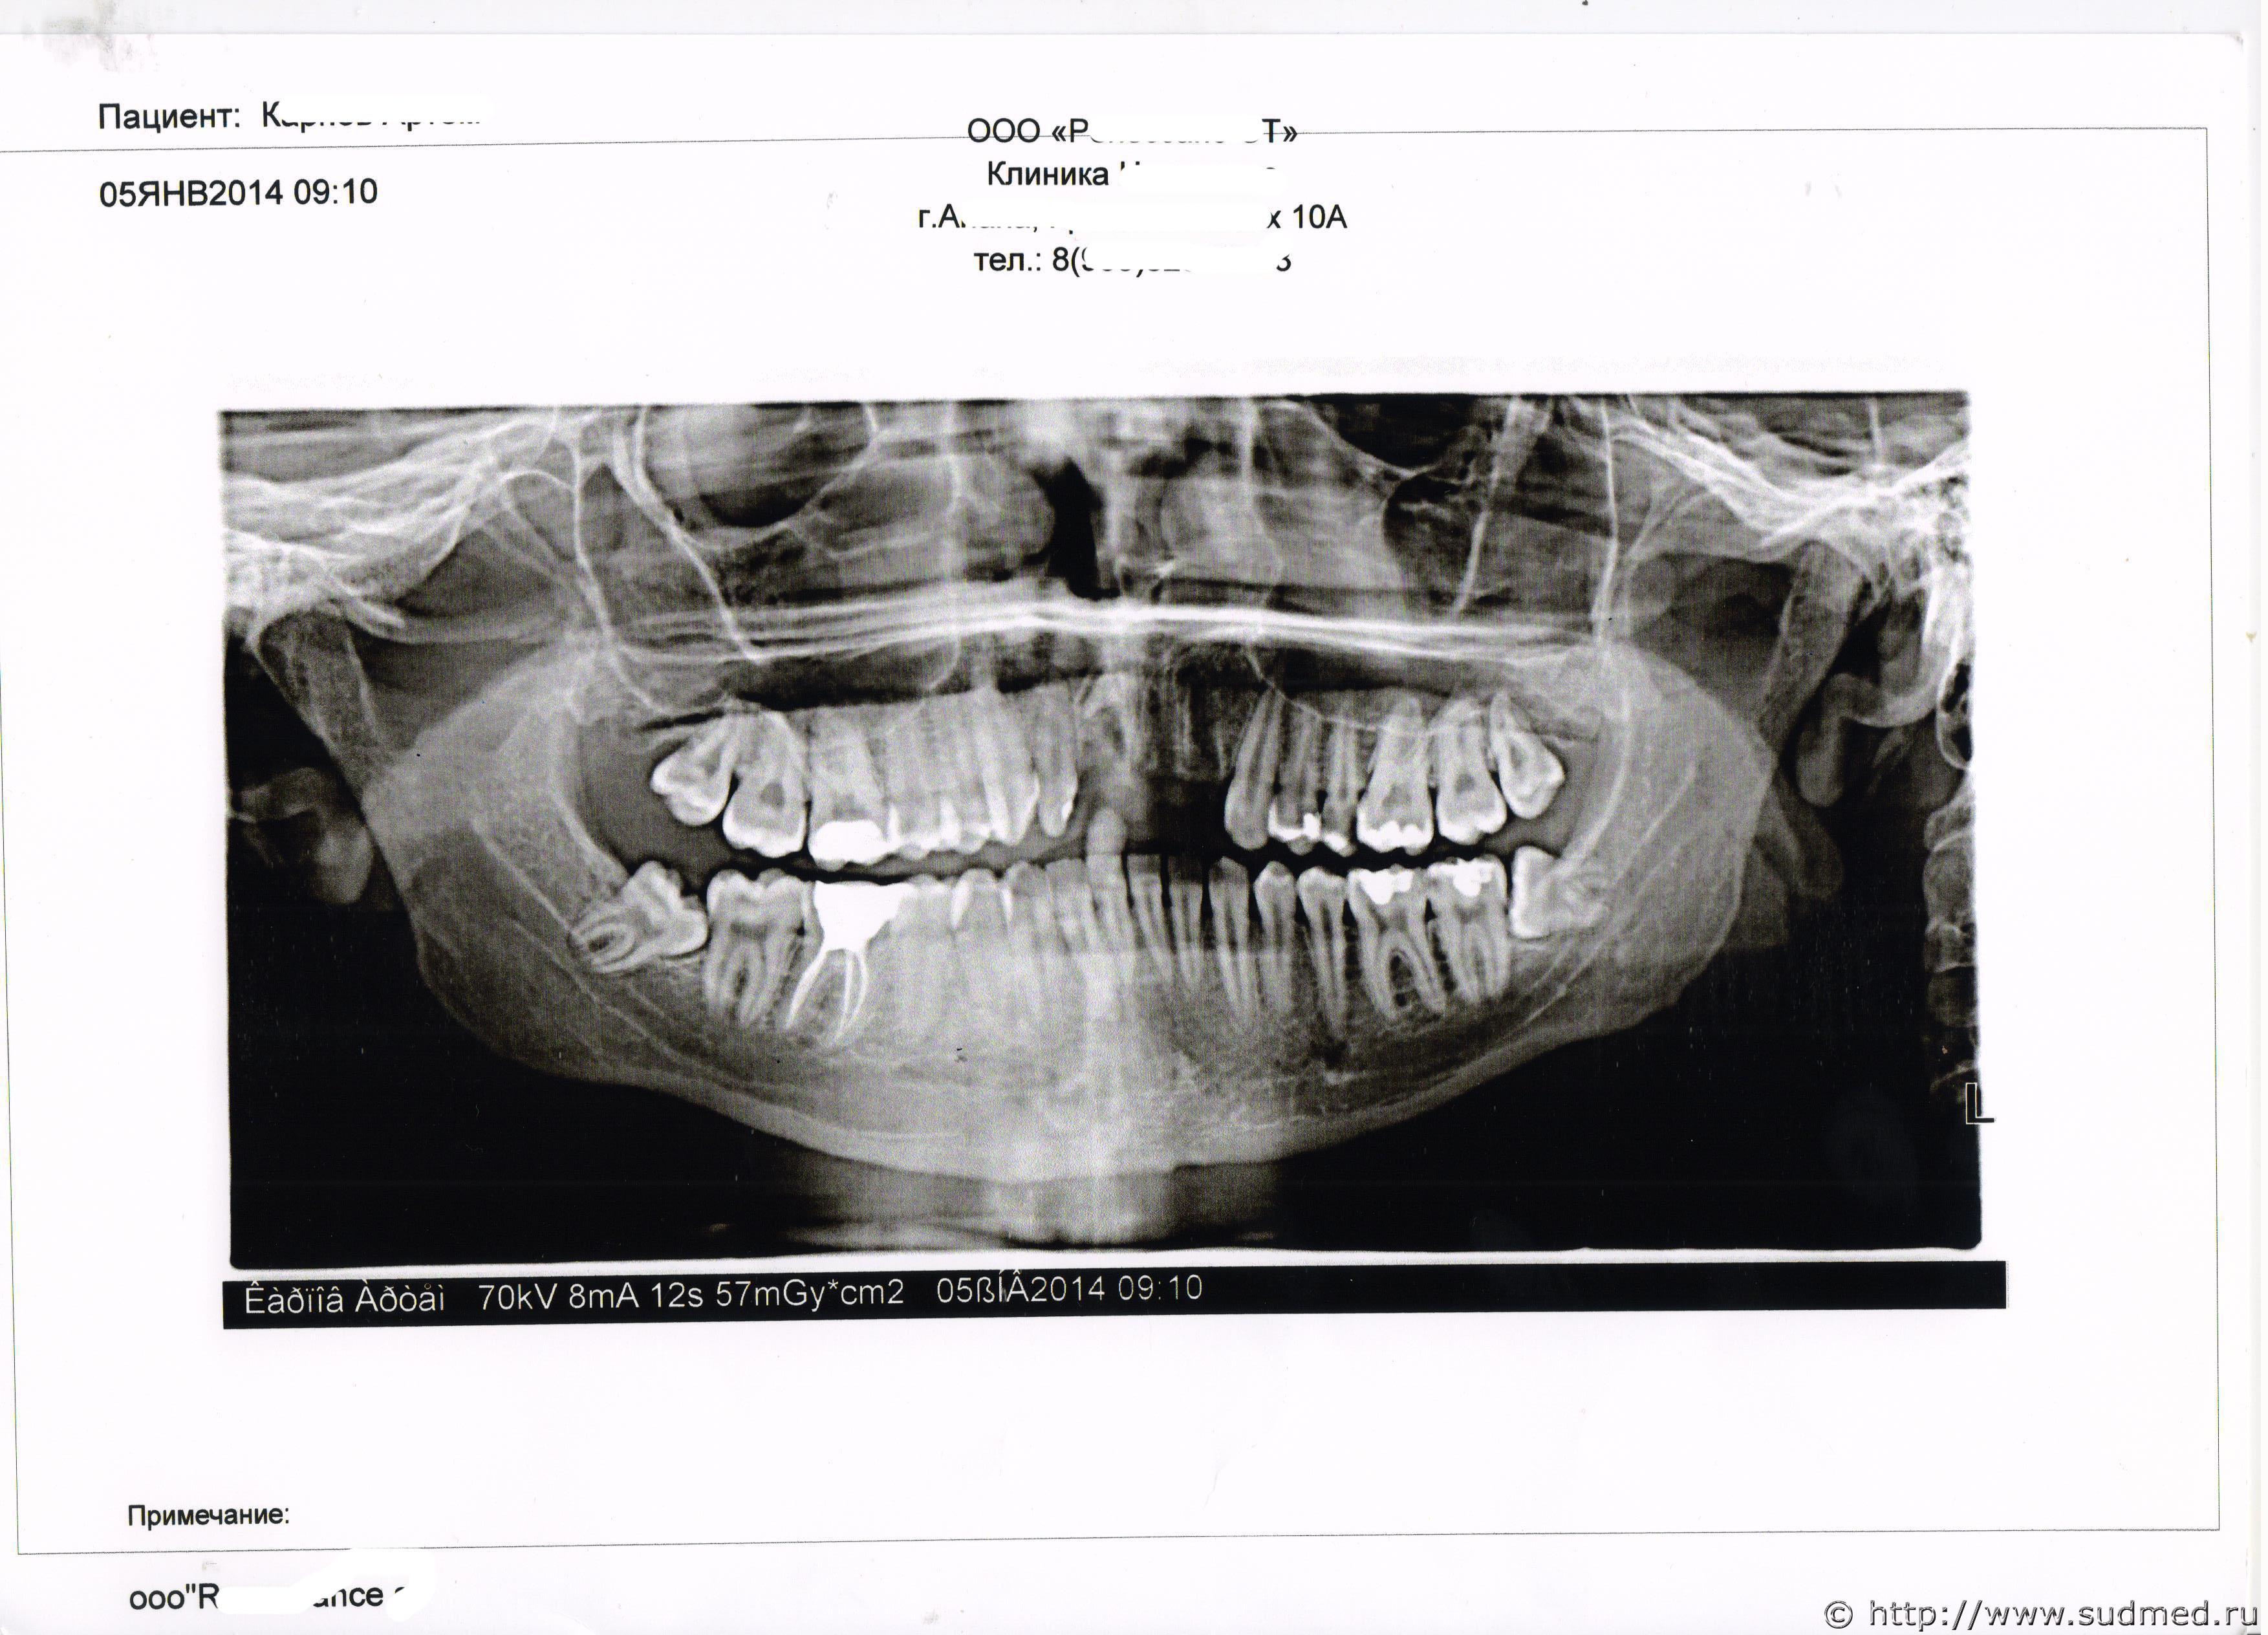

5 января в частной клинике сделана операция по удалению осколков, подкладка костной ткани, десна была ушита(так как врач гос. поликлиники только вырвал вывихнутый зуб, а осколки остались, произошло загноение и т д). Стоматологическую карту прилагаю.

18 января сняты швы.Теперь предстоит долгое лечение, пластика десны, имплантация зубов. История минимум на год с целой серией операций.

Судебная медицина - Прикрепленное изображение